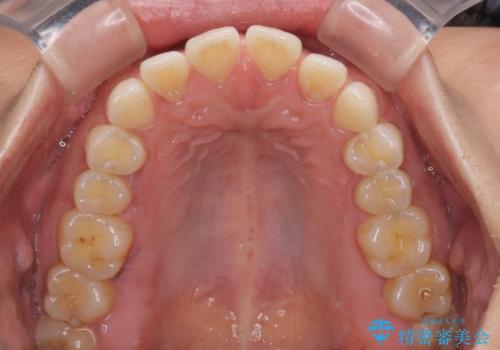

【モニター】前歯のすきっ歯をインビザラインで改善

- 上顎前歯の隙間と口元の突出感を気にして来院された患者様です。

高校生の時に行った矯正治療の後戻りであり、歯列不正は軽度であったので、インビザラインにて治療を行うこととしました。

すきっ歯はあっという間に後戻りを起こすので、可及的に後戻りを防止するために、上下前歯部を舌側からワイヤーで固定しています。

通常は下顎前歯のみに行っていますが、空隙歯列弓では上顎でも行っています。